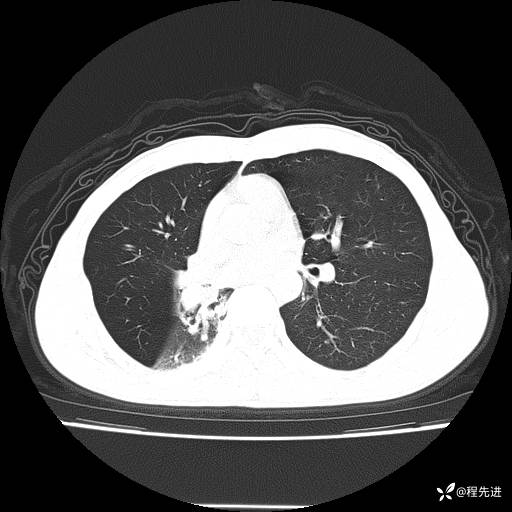

患者性别:男

患者年龄:49岁

主诉:咳嗽、胸痛1周

简要病史:1周前受凉感冒后开始出现咳嗽症状,阵发性连声咳,痰多,黄白痰,不易咳出,伴胸痛、气紧、胸闷,右侧为主,活动用力、呼吸时胸痛明显,曾在当地诊所贴敷膏药仍疼痛

体格检查:T:36.3 ℃ P:80 次/分 R:20 次/分 BP:120/88 mmHg,指脉氧饱和度97%,意识清晰,呼吸平稳,右侧第二、三肋骨压痛,可见膏药贴敷,皮肤无异常,双肺呼吸音粗,未闻及干湿性啰音。心率80次/分,节律整齐,无杂音。腹平软,全腹无压痛无反跳痛

临床诊断:社区获得性肺炎

CT平扫: